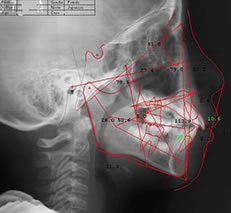

「セファロ」による緻密なあごの分析

セファロは、レントゲン写真のひとつです。一般的なレントゲンが歯全体や上下のあごを撮影するのに対し、セファロでは頭部全体を正面と横から撮影します

歯の傾きや角度、歯列の形態を精密に分析

することで、歯並びと顔全体の調和を考慮した矯正計画を立てることに役立ちます。

どのように歯を動かすべきか、実際にどのように動いたかを、数値的に確認できるため治療の精度が高まります。